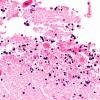

VASCULAR

Herniation, tonsillar (3)